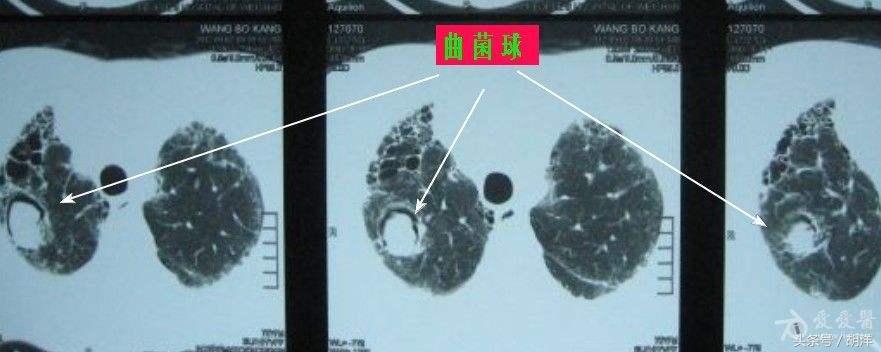

曲菌球

曲霉菌是一种常见的真菌,正常情况下,曲菌很少感染肺部结构正常,免疫力良好的人群,当肺部受到破坏,特别是形成较大空洞和支气管扩张时,曲霉菌可以趁机进入空洞扩张的支气管内与其中渗出的白细胞、纤维素等成分形成球状结构,成为曲菌球,曲菌球在空洞内能够自由的活动,对空洞壁有机械性的损伤,当损伤到管壁变异的血管瘤时,极有可能导致大出血。